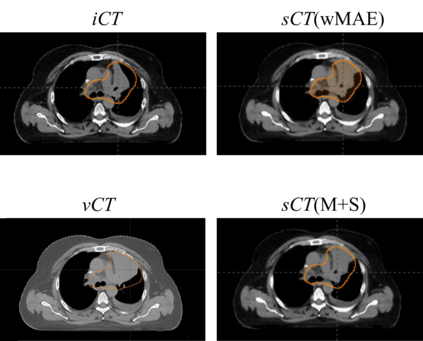

Purpose: In some proton therapy facilities, patient alignment relies on two 2D orthogonal kV images, taken at fixed, oblique angles, as no 3D on-the-bed imaging is available. The visibility of the tumor in kV images is limited since the patient's 3D anatomy is projected onto a 2D plane, especially when the tumor is behind high-density structures such as bones. This can lead to large patient setup errors. A solution is to reconstruct the 3D CT image from the kV images obtained at the treatment isocenter in the treatment position. Methods: An asymmetric autoencoder-like network built with vision-transformer blocks was developed. The data was collected from 1 head and neck patient: 2 orthogonal kV images (1024x1024 voxels), 1 3D CT with padding (512x512x512) acquired from the in-room CT-on-rails before kVs were taken and 2 digitally-reconstructed-radiograph (DRR) images (512x512) based on the CT. We resampled kV images every 8 voxels and DRR and CT every 4 voxels, thus formed a dataset consisting of 262,144 samples, in which the images have a dimension of 128 for each direction. In training, both kV and DRR images were utilized, and the encoder was encouraged to learn the jointed feature map from both kV and DRR images. In testing, only independent kV images were used. The full-size synthetic CT (sCT) was achieved by concatenating the sCTs generated by the model according to their spatial information. The image quality of the synthetic CT (sCT) was evaluated using mean absolute error (MAE) and per-voxel-absolute-CT-number-difference volume histogram (CDVH). Results: The model achieved a speed of 2.1s and a MAE of <40HU. The CDVH showed that <5% of the voxels had a per-voxel-absolute-CT-number-difference larger than 185 HU. Conclusion: A patient-specific vision-transformer-based network was developed and shown to be accurate and efficient to reconstruct 3D CT images from kV images.